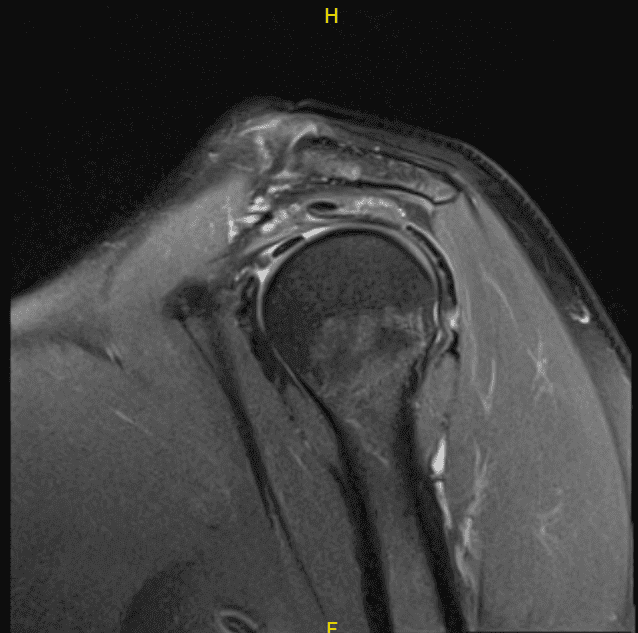

El paciente presentó un resultado de resonancia magnética que mostró tendinosis del manguito rotador multifocal con una rotura intrasustancial de inserción intrasustancial de alto grado y grosor parcial de alta delaminación en la confluencia de los tendones supraespinoso e infraespinoso.

Tendinosis leve de la porción intraarticular del tendón del bíceps. Degeneración leve con deshilachado/desgarro en la base del labrum superior. Artrosis articular acromioclavicular muy leve. Bursitis subacromial-subdeltoides leve.

MRI-3T hombro izquierdo sin contraste